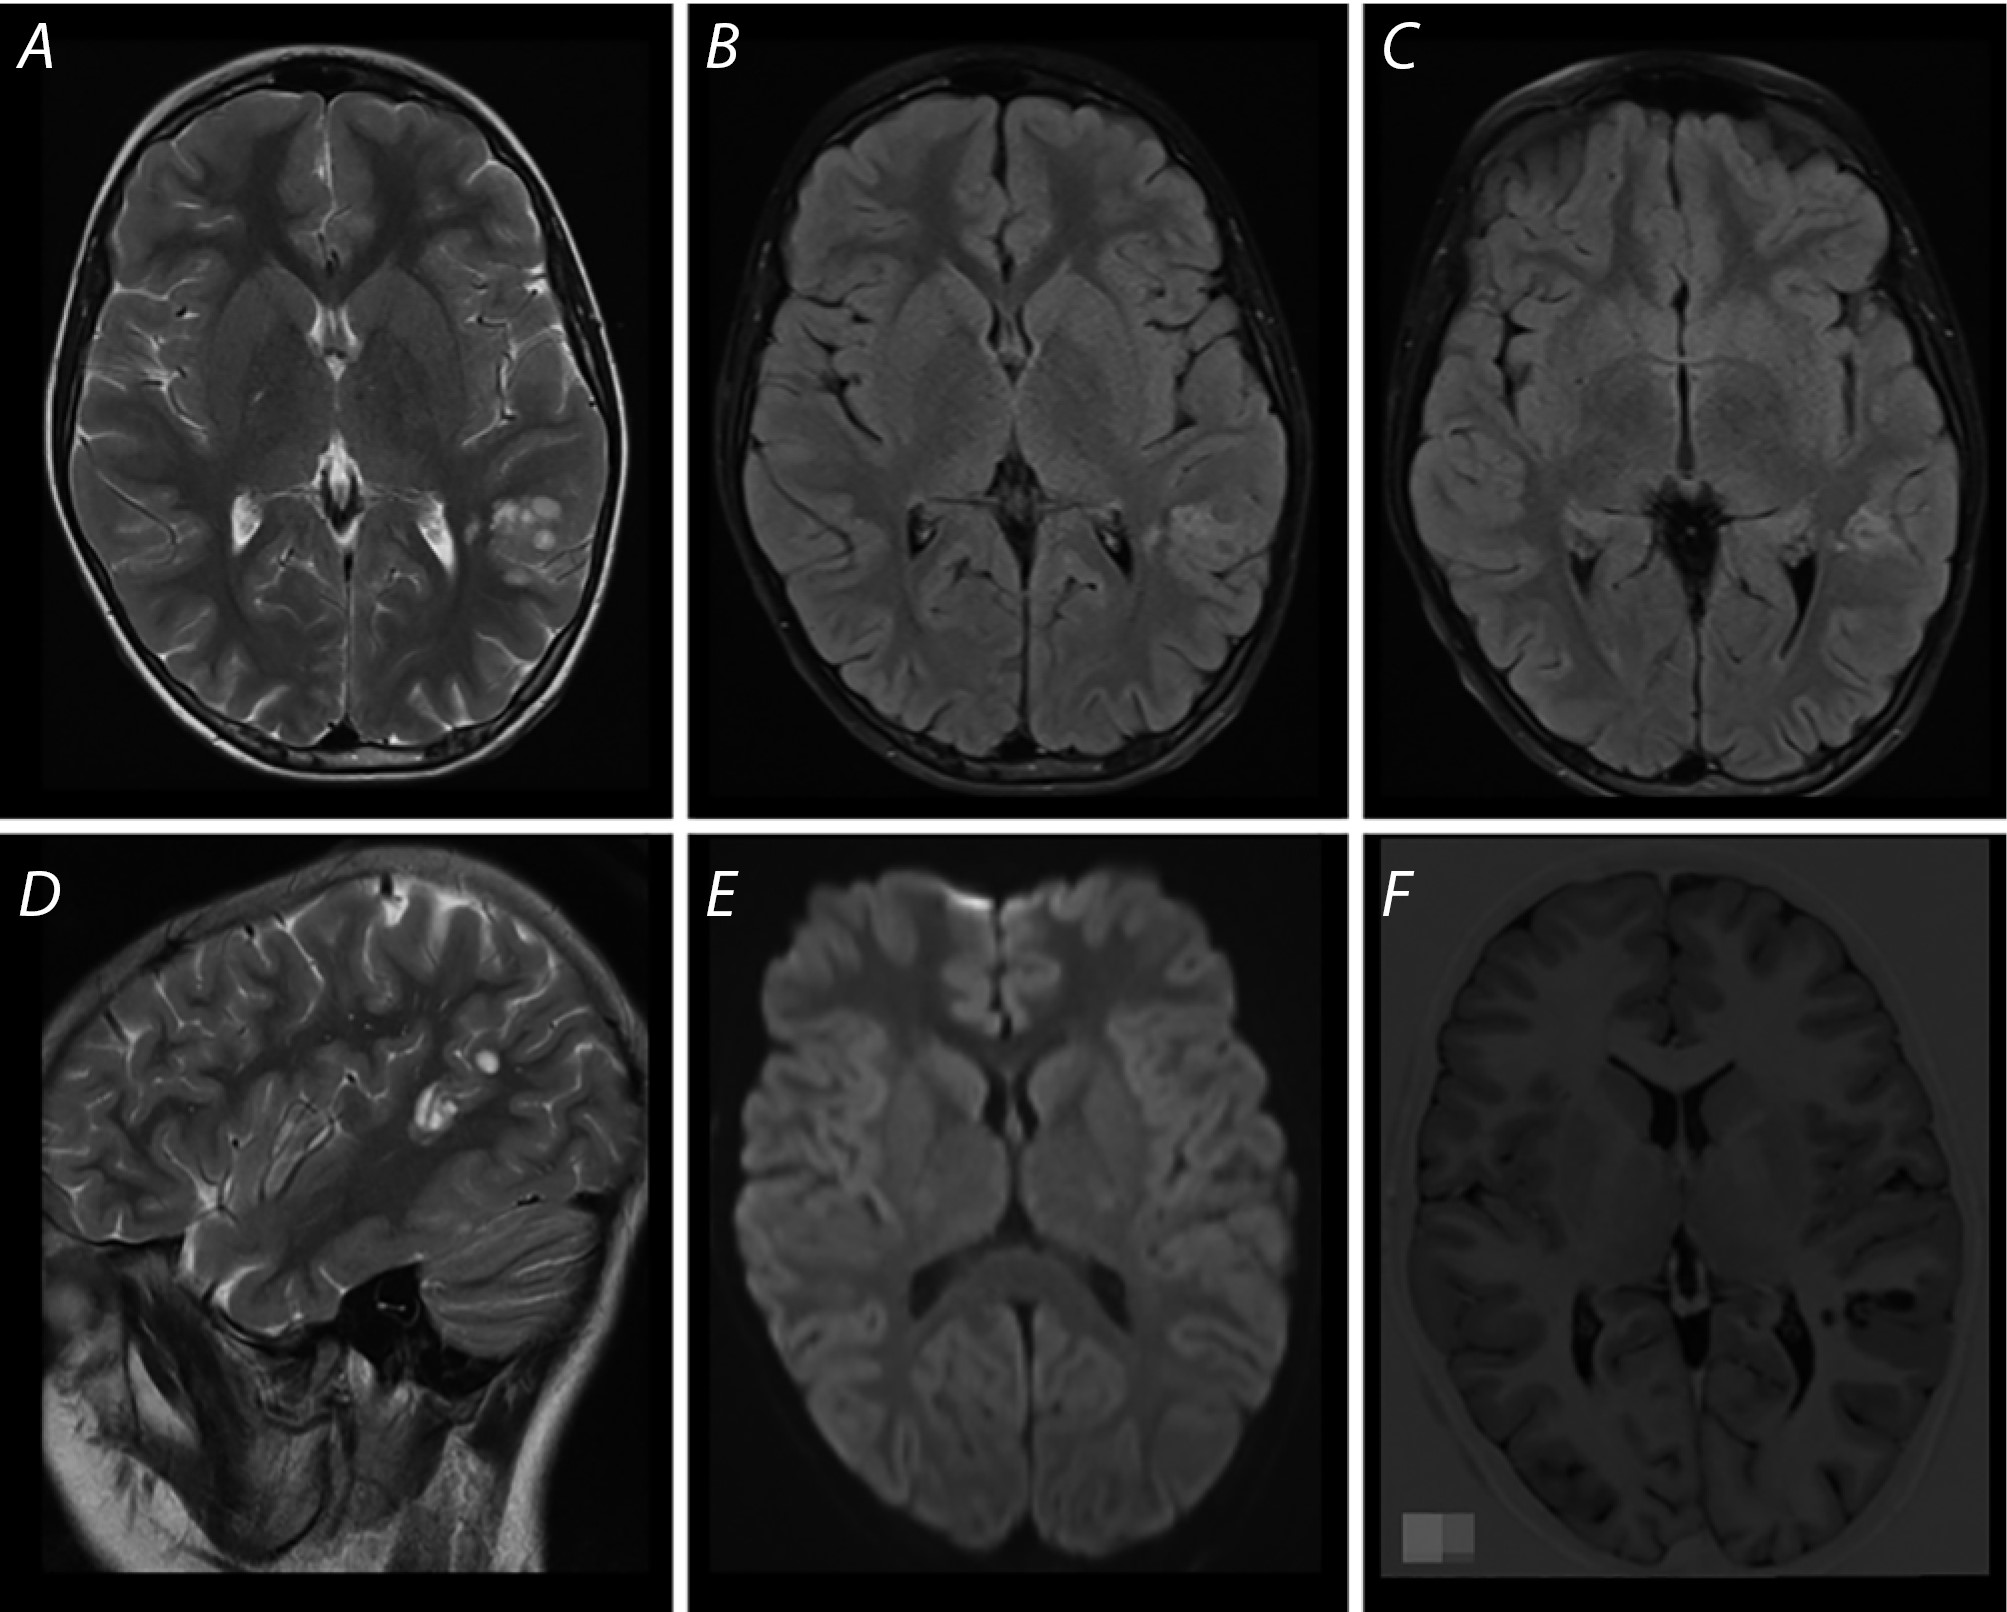

Рис. 1. МРТ головного мозга пациента Г. при первом обследовании.

Дополнительное образование в заднелатеральных отделах левой височной доли с вовлечением теменной доли с характерной для ДНЭО мультикистозной структурой («soap-bubble pattern»), субкортикально/кортикальной локализацией и трансмантийным распространением в область заднего рога гомолатерального бокового желудочка (А, В, С). На сагиттальных срезах отчётливо определяется вовлечение теменной доли левого полушария (D). Образование не демонстрирует рестрикции диффузии и перифокальной реакции (E). На изображениях Т1 SPC ISO с толщиной среза 1 мм отчётливо визуализируются мультикистозное строение образования и преимущественная локализация в кортикомедуллярной зоне (F).

Fig. 1. Brain MRI of patient G. at his first examination.

A lesion is seen in the posterolateral area of the left temporal lobe with involvement of the parietal lobe, with a multicystic structure (“soap-bubble pattern”) typical for DNET, with subcortical/cortical location and transmantle spread to the posterior horn of the homolateral lateral ventricle (А, В, С). On sagittal slices, involvement of the parietal lobe of the left hemisphere is clearly seen (D). The lesion does not demonstrate restricted diffusion or perifocal reaction (E). T1 SPC ISO images with a slice thickness of 1 mm clearly show the multicystic structure of the lesion and its predominant location in the corticomedullary area (F).